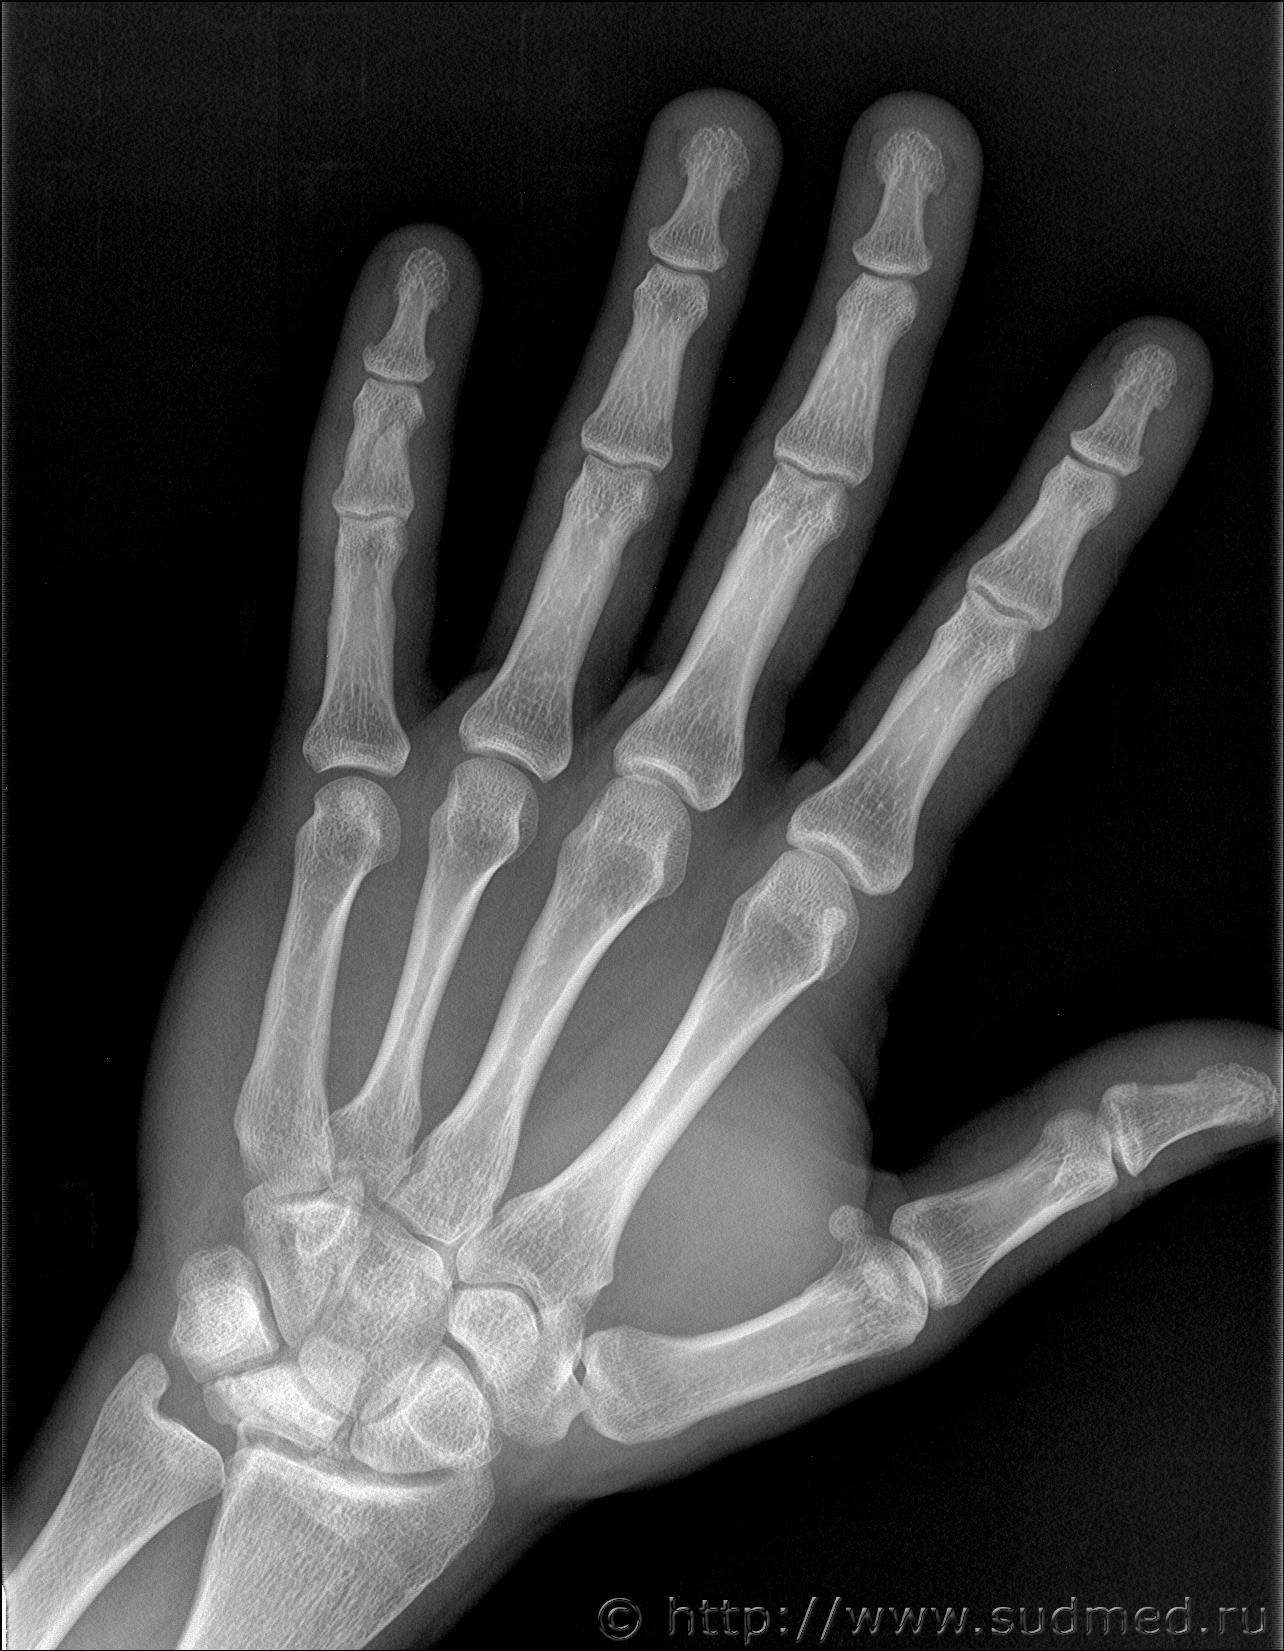

Здравствуйте. Произошла драка в которой когда я упал и меня пинали по голове, я закрыл голову рукой и нападавший попал ногой по руке. В результате он повредил мне мизинец на левой руке. Врач скорой сказала что это скорее всего ушиб. Я думал что ушиб пройдет, но палец болел и через 13 дней я обратился в травмпункт, мне сделали рентген кисти и обнаружили «З/консолидирующийся перелом о/фаланги Vп левой кисти». По этой справке мне определили средний вред здоровью. Потом когда суд мед эксперты смотрели данный снимок они не нашли перелома. Снимок сделан в травм пункте на 13 день после травмы. Можете ли вы оценить снимки. Что на них видно? Какая степень вреда здоровью?

Скорее всего технический сбой. Вот изображения в другом формате.

Достоверно перелома не видно.

Еще один снимок делал но там 3 месяца прошло и он на пленке. А почему достоверно перелома не видно? Травматолог и глав врач травматологии сказали что точно перелом.

В справке из травм пункта на 13 день после травмы указано:

Установлен диагноз: З/консолидирущийся перелом о/фаланги Vп левой кисти.

По поводу первого снимка, 13 дней после травмы. На диске, цифровой.

Заключение: на представленных рентгенограммах 5 пальца левой кисти от (13 дней после травмы) на электронном носителе костно-травматических изменений не выявляется.

Снимки цифровые 13 дней после травмы:

Больше вопросов и предположений вызывает не основная, а средняя фаланга. Если бы она так выглядела через 100 дней после травмы, можно было бы согласиться, что несколько месяцев назад был перелом средней фаланги. Через 13 дней перелом так выглядеть не может. Вероятно, имеется какая-то индивидуальная особенность или когда-то давно (многие месяцы-годы назад) был перелом средней фаланги мизинца. Основная фаланга особых вопросов не вызывает: согласен с рентгенологами по поводу отсутствия достоверных рентгенологических признаков перелома.